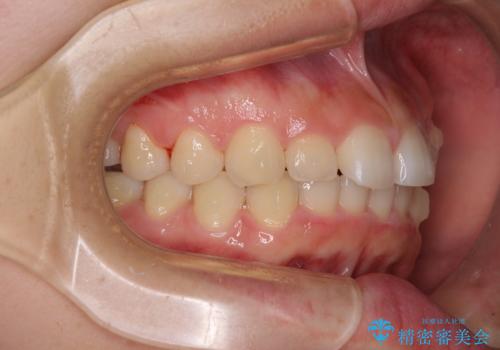

前歯のデコボコと突出感 インビザラインによる矯正治療

- 上下前歯のデコボコと、上顎前歯の突出感を気にして来院された患者様です。

インビザラインによる上下歯列の側方拡大と後方移動、IPR(歯と歯の間を削る)にるスペースの獲得により歯列を整えることとしました。

毎日22時間以上しっかりとマウスピースを装着していただいたので、スムーズに治療が進みました。歯と歯の間を削ることでうまくスペースコントロールでき、1年強で終えることができました。